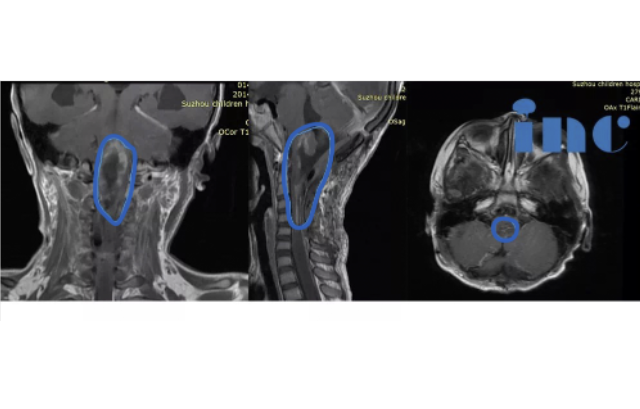

治疗过程:此时正值INC巴特朗菲教授来华开展示范手术交流期间,琦琦一家得知巴特朗菲教授对于此类复杂疑难位置肿瘤有丰富的成功手术经验,于是选择咨询教授,教授回复至少可以切除95%以上的肿瘤,于是巴教授主刀在国内合作医院苏州大学附属儿童医院手术团队的配合下,肿瘤次全切(95%以上),手术顺利,手术历时8小时。

术后情况:术后ICU留观1天,神志清楚,完全自主呼吸,拔除插管,生命体征平稳,转入普通病房。患儿右侧肢体活动度、肌力较术前明显好转。术后1周,患者下地自行行走,无手术并发症出现。术后3周出院,术后2月可如同龄患儿生活。琦琦父母也会定期在术后向INC发送七七的恢复状况视频,他们一家人对INC以及巴特朗菲教授更是充满了感激,曾多次微信致谢。